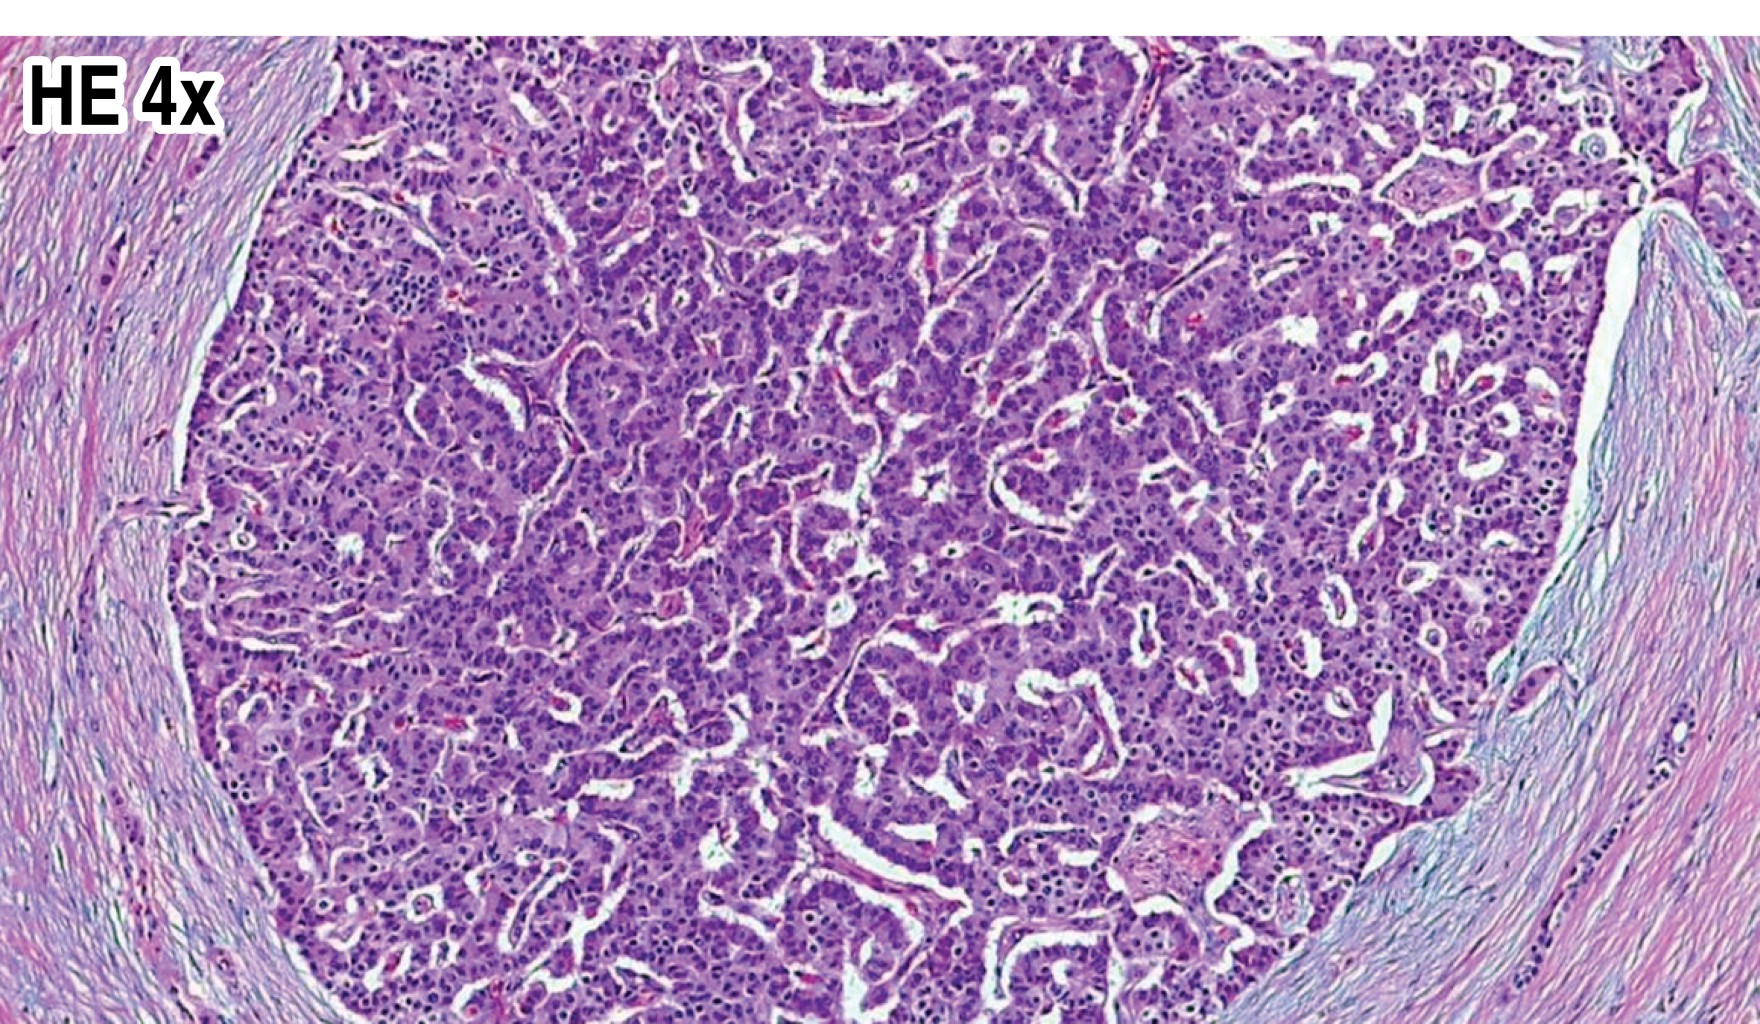

En múltiples ocasiones requirió atención en el servicio de urgencias dónde se evidenció la presencia de hipoglucemia tratada con solución glucosada que mejoraba el cuadro clínico. En general la exploración física dentro de parámetros normales, peso de 90 kg, talla 170 cm, índice de masa corporal (IMC) 31.1. Como parte del abordaje diagnóstico se realizó una prueba de ayuno que se tuvo que suspender después de 18 horas por síntomas neuroglucopénicos. Se identificó hiperinsulinismo sérico con glucosa de 56 mg/dL, insulina de 79 Uu/mL, péptido C de 10.2 ng/mL y relación insulina/glucosa de 13.1. Se solicitó una tomografía computada helicoidal trifásica, la cual demostró un nódulo redondo, de contornos bien delimitados, sólido, de localización superficial en la porción distal de la cola del páncreas que mide 12.9 mm de diámetro, hipodensa en la fase arterial e hiperdensa en las fases porta y principalmente en la fase venosa, la opinión radiológica fue de sospecha para insulinoma (Figura 1). Por las conclusiones de los estudios de imagen, la paciente se programó para pancreatectomía distal por laparoscopia que se realizó sin complicaciones. El estudio histopatológico reportó un fragmento de páncreas de 3.5 × 3 × 2.5 cm, amarillo rosado, se identificó lesión esférica, única de superficie gris violácea de 1.5 × 0.9 × 0.9 cm. Se identificó hiperplasia de los islotes pancreáticos y células endócrinas aisladas, así como bazo accesorio en la cola del páncreas. La inmunohistoquímica reveló positividad a sinaptofisina y cromogranina en los islotes pancreáticos de Langerhans con un índice de proliferación ki67 de 1%. Con todos estos datos se realizó el diagnóstico de nesidioblastosis difusa (Figuras 2 y 3). En este momento el paciente se encuentra con adecuado control glucémico y remisión de los eventos neuroglucopénicos.

Figura 1